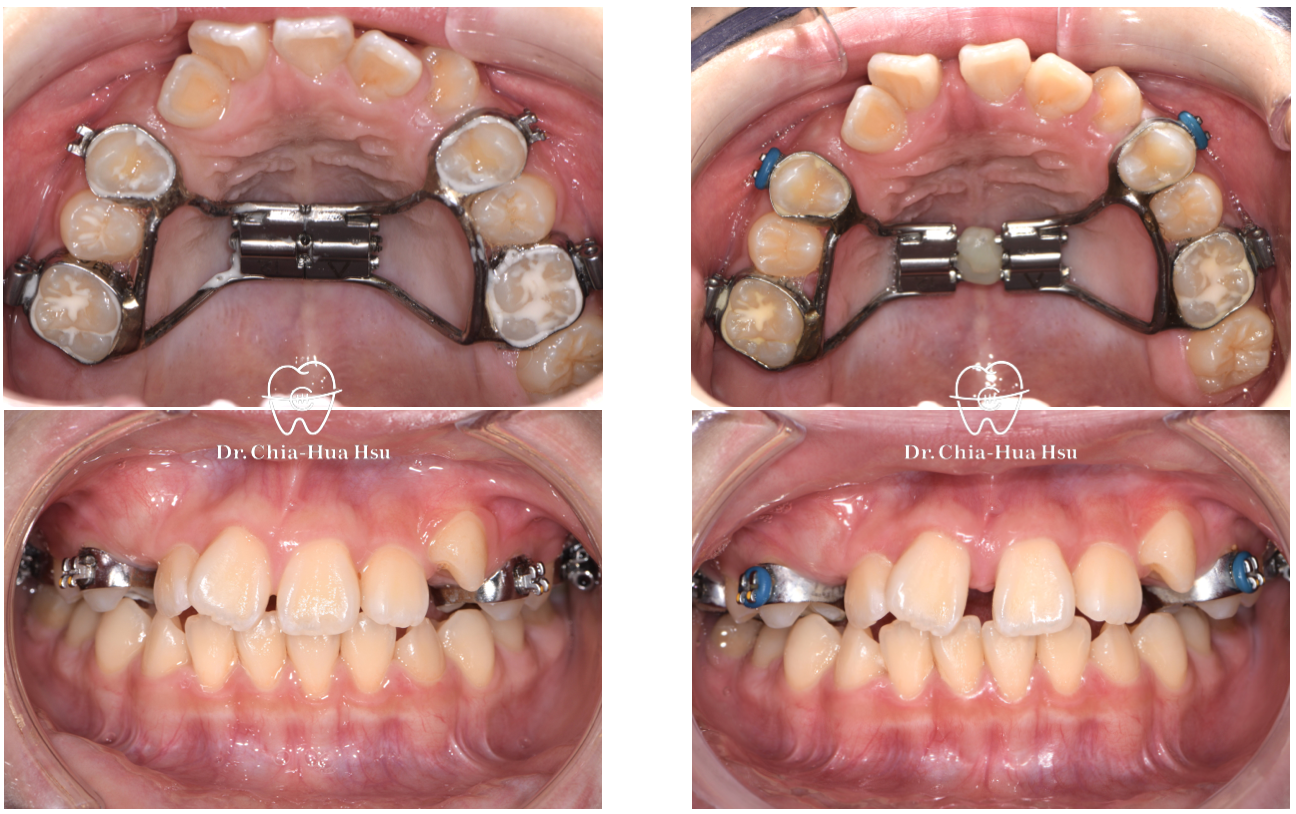

上顎擴弓前

上顎擴弓後

使用上顎擴弓器將上顎牙弓撐寬,一天兩轉(早晚各一次),每轉一次大概可以撐寬 0.25 cm。

大概二至四週後,門牙之間會有明顯縫隙出現,代表上顎骨縫有成功撐開!上顎撐寬後,就可以把擁擠的牙齒排進牙弓中囉!